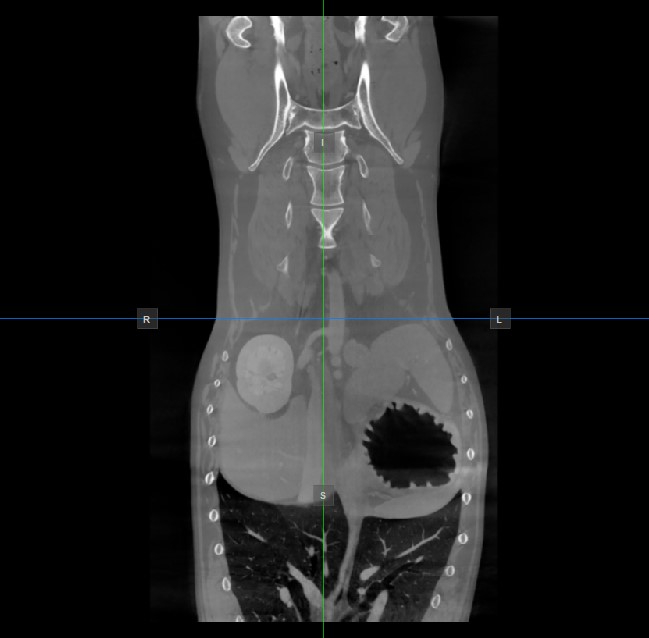

Image Orientation and Image Planes¶

The position and intersection of the other two image planes not represented in the active viewport is indicated by two vertical and horizontal lines called slicers. The endpoints of each slicer are labeled with a letter that corresponds to the appropriate direction/side of the 3D volume, based on the RAS coordinate system.

Only four sides of the available six are indicated on each 2D viewport. The labels and the corresponding side are the following:

Patient Right (R), indicating the right side of the body

Patient Left (L), indicating the left side of the body

Anterior (A), indicating the front side of the body

Posterior (P), indicating the back side of the body

Superior (S), indicating the top side of the body

Inferior (I), indicating the bottom side of the body